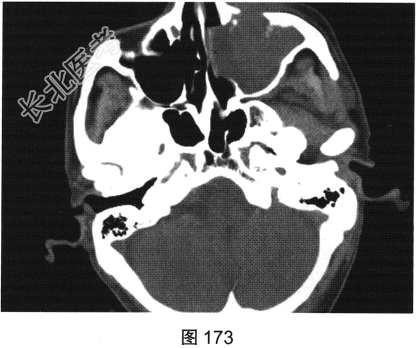

- [材料题] 患者男性,75岁。左侧颌面部肿胀6个月,局部压痛,伴有左侧鼻塞、流涕。CT检查结果如图173~图176所示。

- 简答题1、请问该患者CT表现是什么?

- 简答题2、请问最符合该患者的初步诊断是什么?

- 简答题3、请问属于上颌窦恶性肿瘤有哪些?

- 简答题4、请问翼腭窝受侵主要见于哪种疾病?